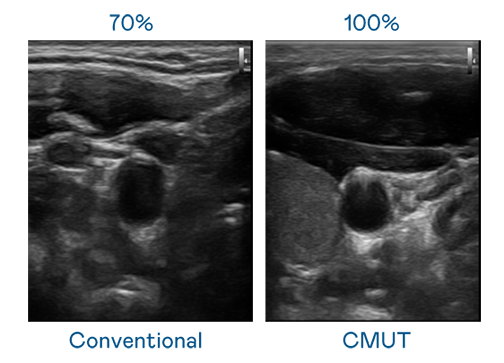

CMUT 技术是一种用电容式微机电元件来产生超音波讯号的技术。与传统 PZT 压电式技术相比,CMUT 频宽增加 30%,更宽频的超音波讯号让影像解析度大幅提升,是实现高影像品质医疗超音波扫描、促进精准医疗发展的关键技术。

大频宽带来超清晰影像

超音波影像的解析度高低,首先取决于探头能发出的讯号频宽。1277星际电子 CMUT 可提供高清晰的超音波讯号,提供高频宽、高灵敏度、影像纹理细节更高的超音波影像,协助医护人员缩短影像判读时间及利用精准的医疗影像进行诊断。